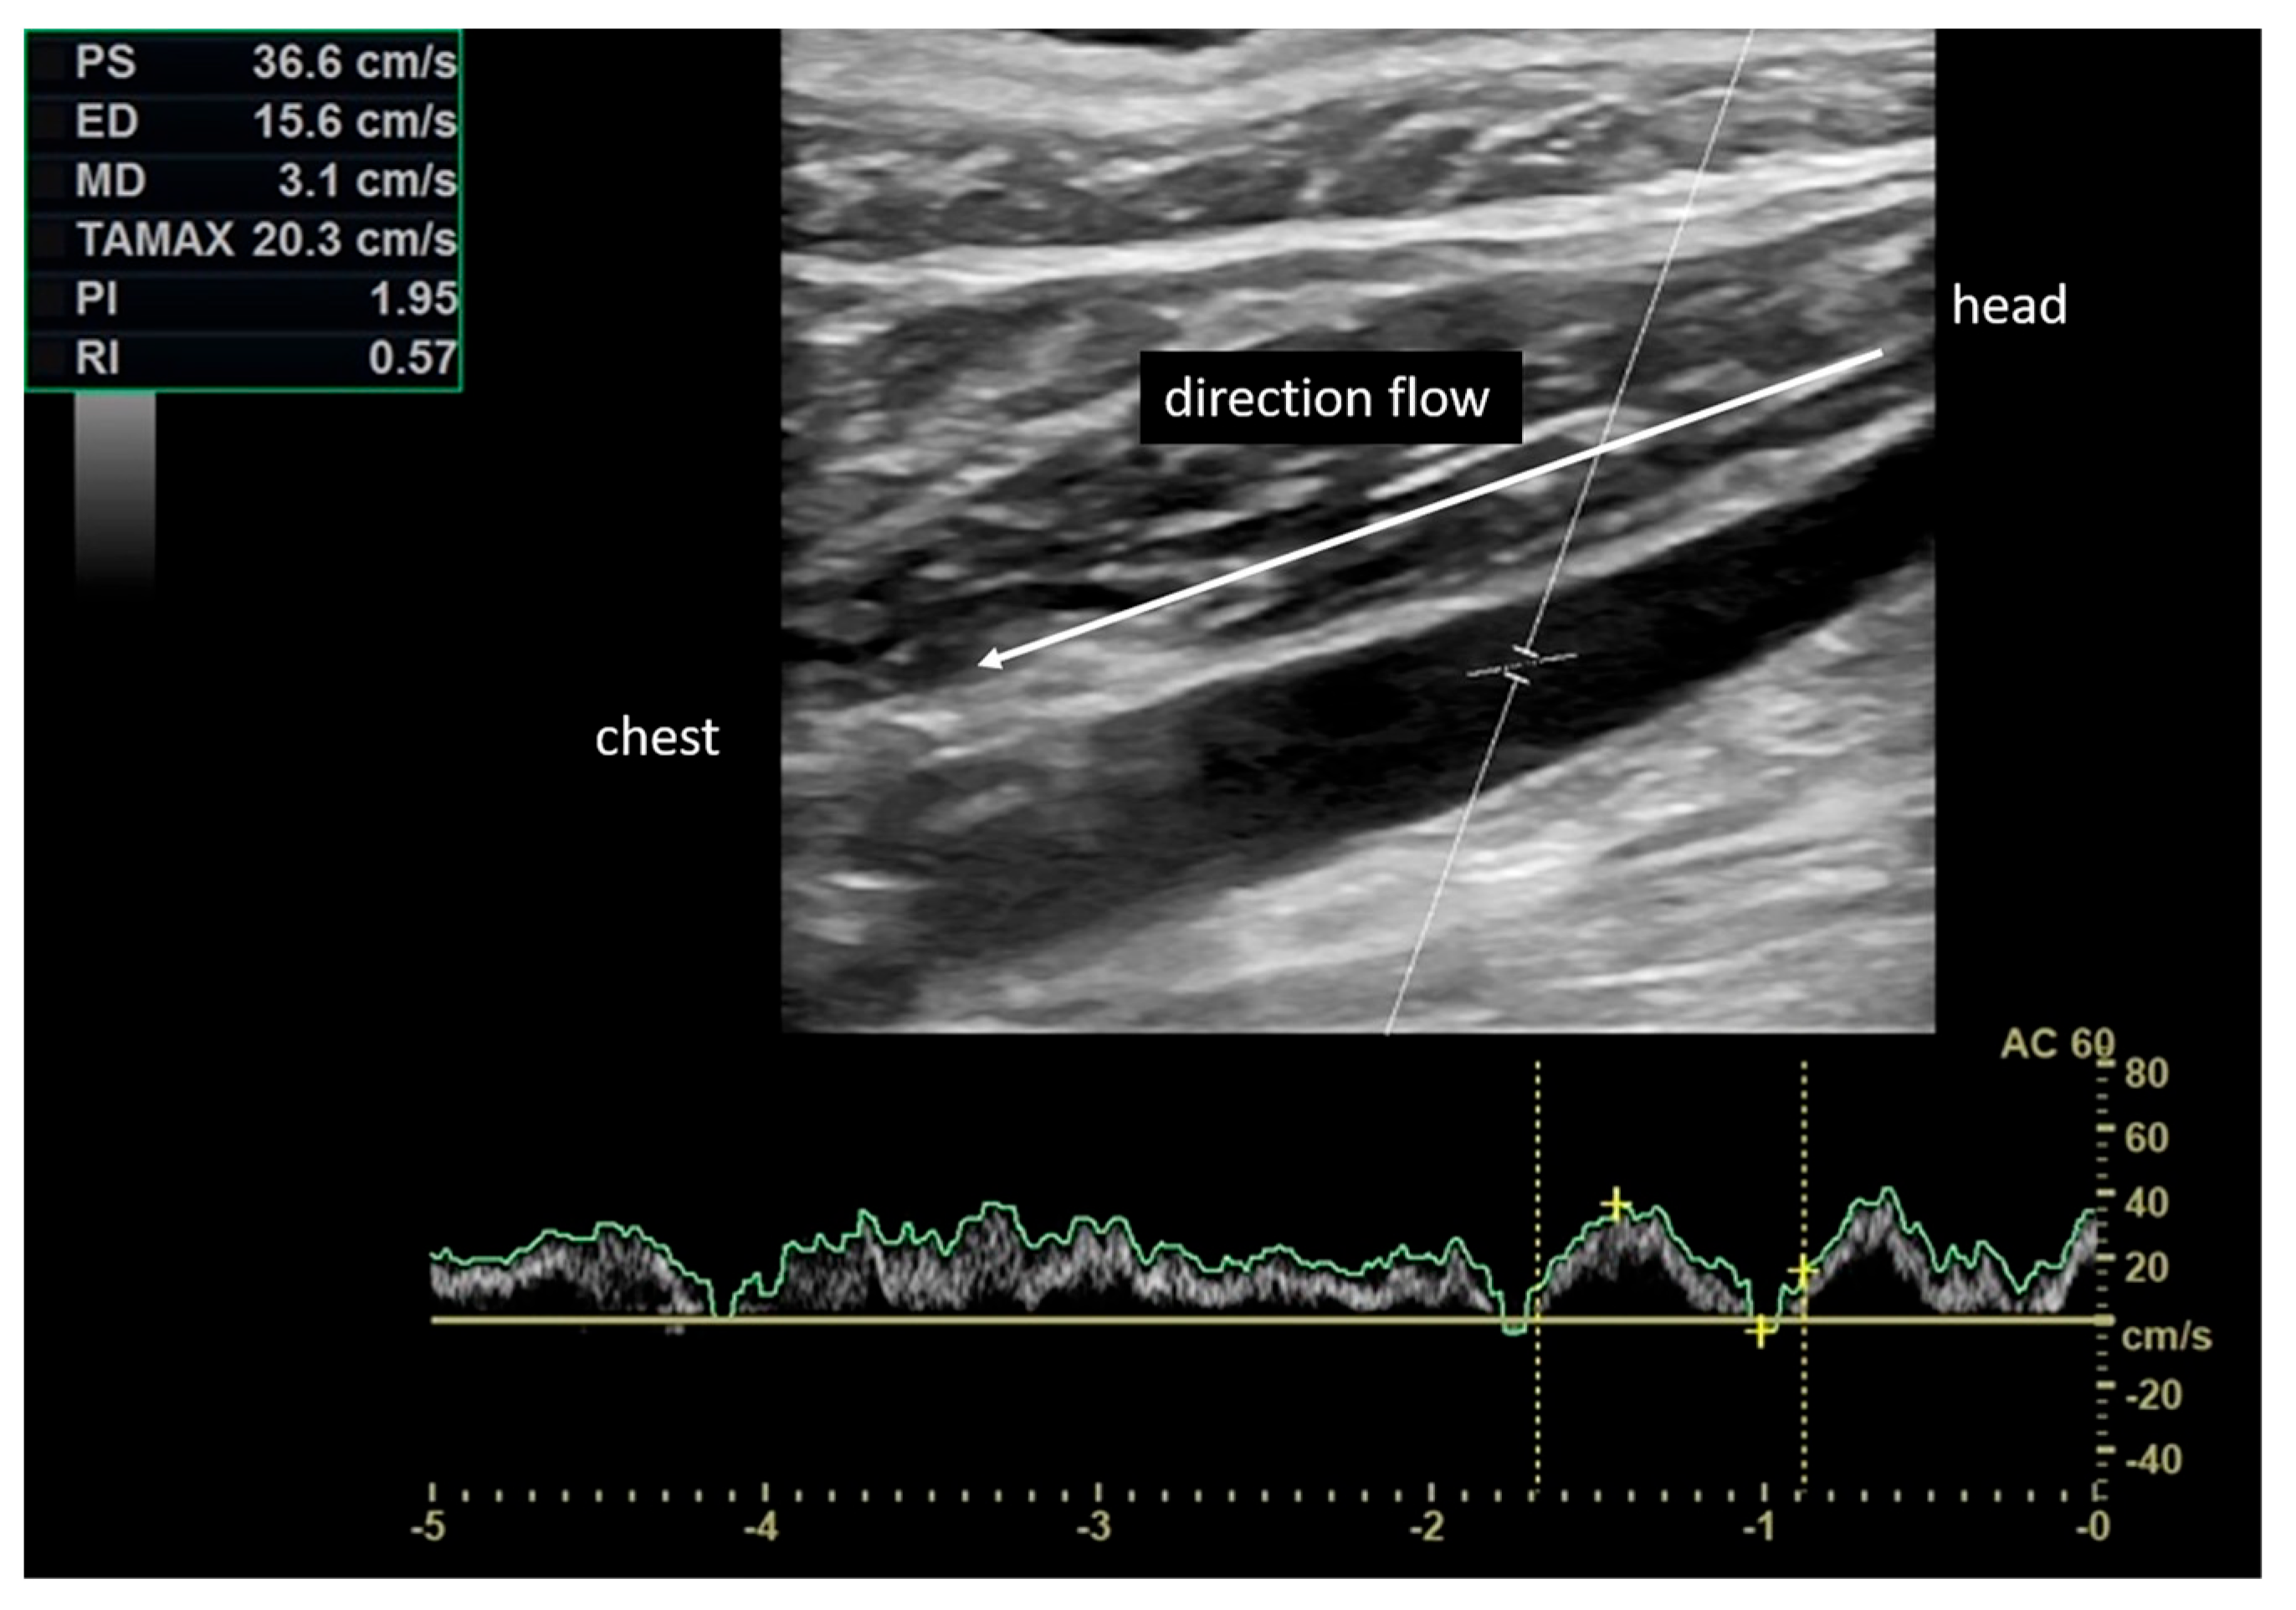

2.4. Vascular Assessment